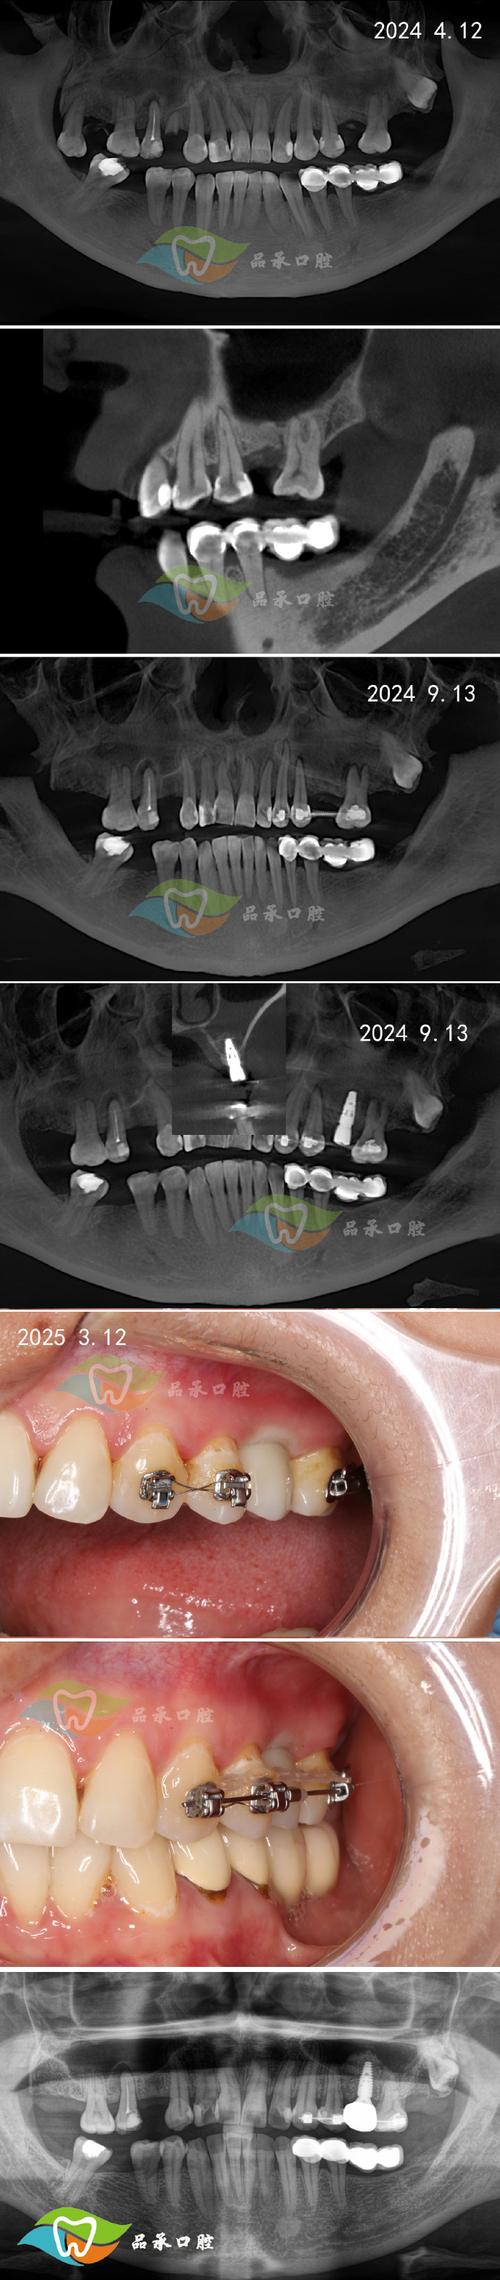

远期骨吸收与种植失败

即使初期骨结合成功,长期低骨密度状态下,骨改建失衡,破骨细胞活性相对高于成骨细胞,会导致种植体周围骨持续吸收,临床表现为种植体周袋形成、牙龈退缩、X光片显示牙槽骨高度降低,最终可能因支持骨量不足导致种植体失败,需重新植骨甚至拔除种植体。 -

精准骨密度检测

术前除常规CBCT(锥形束CT)评估骨量外,建议结合骨密度检测技术,如采用双能X线吸收测定法(DXI)测量颌骨骨密度,或通过CBCT灰度值分析(Hounsfield unit,HU)间接评估骨质量,研究显示,HU值>850提示骨密度良好,400-850为中等密度,<400则为低密度,需制定针对性方案。 -

定期随访与骨监测

术后每年进行CBCT复查,测量种植体周围骨吸收量,若年骨吸收>0.2mm,需及时干预,如洁治、调合,必要时进行植骨或更换修复体。